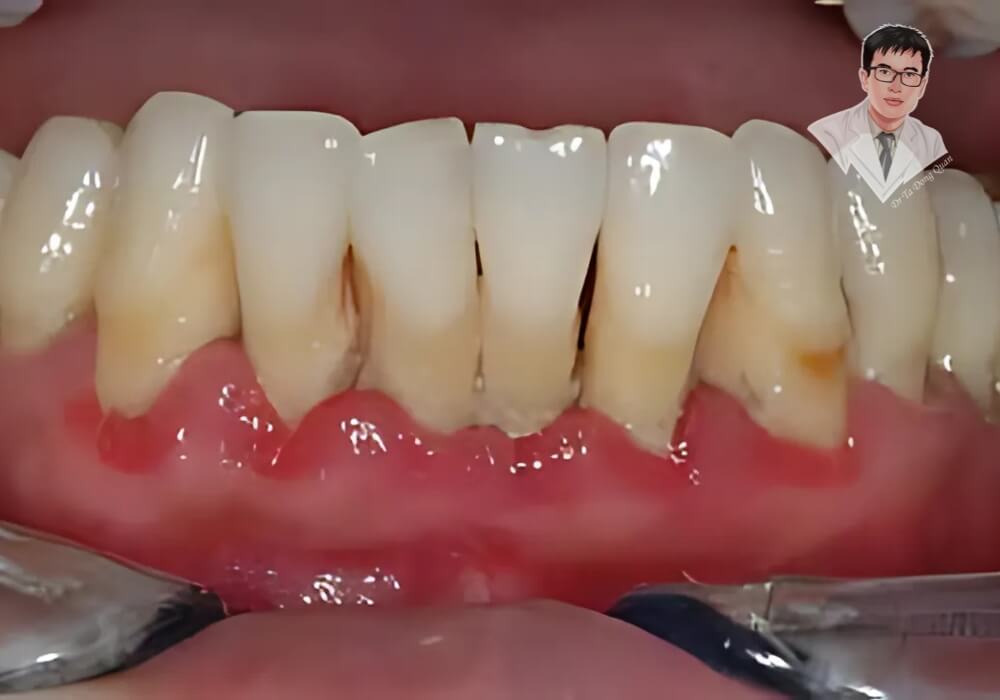

1. Chân Răng Lộ Rõ

Dấu hiệu dễ nhận biết nhất của bệnh tụt nướu răng là răng trông dài hơn bình thường do phần chân răng bị lộ. Khi mô nướu co rút, không còn che phủ hết chân răng, răng trở nên nhạy cảm hơn và dễ bị tổn thương.

- Quan sát thấy răng có vẻ dài hơn so với trước đây.

- Xuất hiện các khe hở giữa răng, tạo điều kiện cho thức ăn mắc kẹt.

4. Nướu Sưng Đỏ, Đau Nhức

Tụt nướu răng không chỉ làm lộ chân răng mà còn khiến nướu dễ bị viêm nhiễm. Khi vi khuẩn tấn công, nướu có thể sưng đỏ, đau nhức và trở nên nhạy cảm hơn.

- Nướu có màu đỏ thẫm thay vì hồng nhạt.

- Xuất hiện cảm giác đau hoặc nhức nhẹ ở vùng nướu bị tụt.